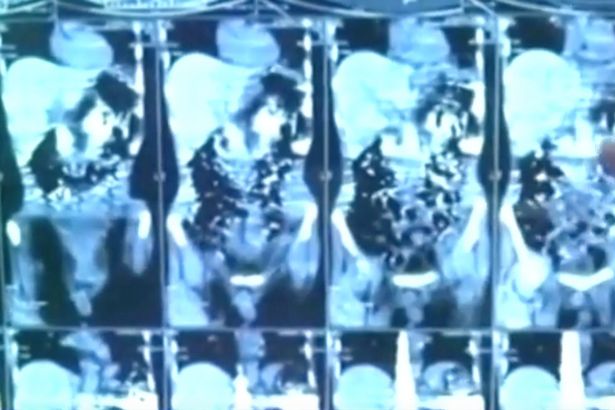

Vietbf.com - Một người đàn ông Ấn Độ đã bị mắc hội chứng ăn uống khá kỳ lạ khi người đàn ông này lại ăn 40 con dao, nên đã phải nhập viện khẩn cấp vì quá đau bụng, nhưng vì người đàn ông giải thích đơn giản: “Chỉ là tôi thèm ăn dao, nên tôi ăn thôi”.

Để giải cơn khát này, anh đã nuốt 40 con dao vào bụng, và vẫn sống sót.

Các bác sĩ đã giải phẫu và lấy ra số dao người này đã nuốt suốt hơn 2 tháng qua.

Các ảnh chụp X-quang dạ dày của bệnh nhân khiến các bác sĩ kinh ngạc khi nhìn thấy hơn 40 mảnh kim loại.